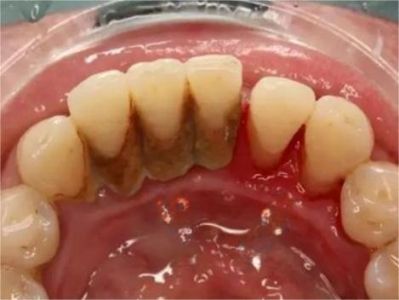

牙龈退缩牙龈萎缩露出牙根图

牙龈退缩发作于上排尖牙和磨牙处,导致牙根暴露在外,伴有牙齿松动、口臭、牙根面敏感等症状,是由于刷牙不当、牙周炎等因素引起。